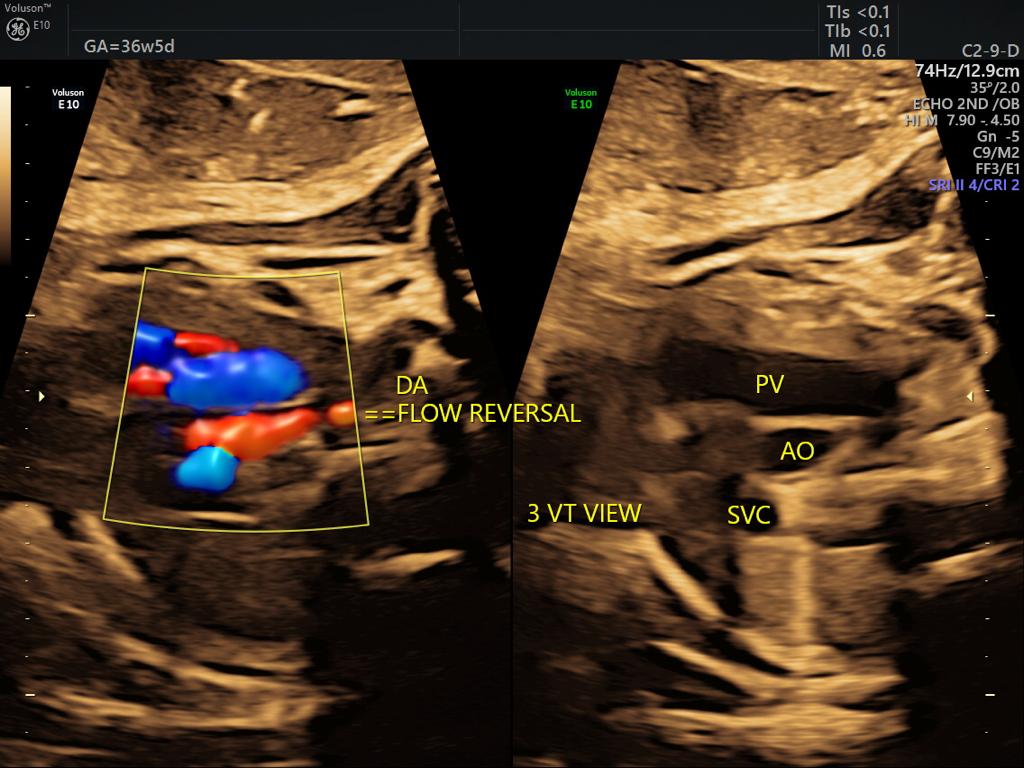

One of the most important scans done during pregnancy is during the second trimester, between weeks 18 and 20. This is called the targeted anomaly scan and is essentially a complete head to toe analysis of the fetus in a clinical perspective. Even though the scan might not be able to identify every single issue, however, gynaecology specialists in Guntur use this scan to validate and rule out any discrepancies with respect to most of the major organs in the Childs body including the brain, kidneys, bones, heart as well as the spinal cord and face, etc. The measurements with respect to every organ are taken also another important aspect of this scan is to identify how the placenta is placed and if it is tending towards creating an issue later on. Visit ultra sound test centers in Guntur at fertility hospitals.

Sometimes improper growth could be a cause of concern and on the other side, there are certain disorders which are identified in this scan, some could be rare congenital heart anomalies related to fetalbrain,face, thorax,heart,GIT,renal, skeletal etc